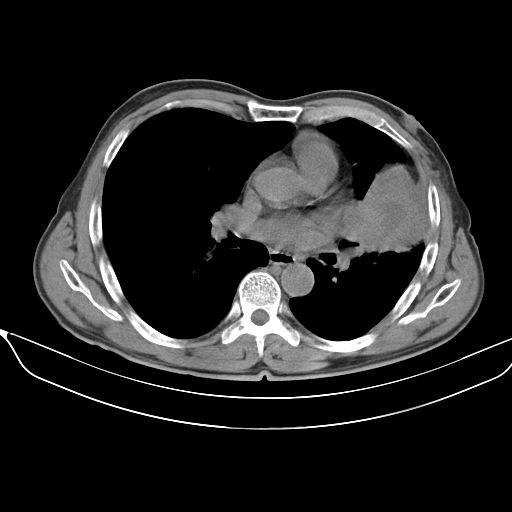

以下是引用shuiyuan在2010-3-1 10:45:00的发言:[br]考虑左肺上叶中心型肺癌伴阻塞型炎症,邻近胸膜受侵。

以下是引用心路寻觅在2010-3-1 10:23:00的发言:[br]1、考虑左肺上叶周围型肺癌[br]2、右上肺陈旧性病灶。[br][br][本贴已被 心路寻觅 于 2010-3-1 10:40:18 修改过]